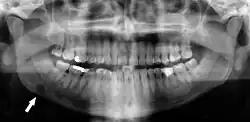

Panoramic radiograph showing Stafne defect (arrowed).

Dental panoramic radiograph showing dentigerous cyst (arrowed).